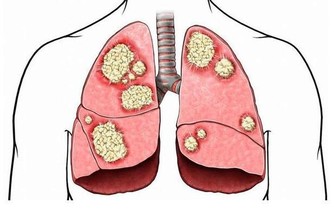

據美國紐約一家專門從事癌癥研究的權威機構透露,中國和日本婦女乳腺癌的發病率比西方低得多,這是為什麼呢?

科學家在比較了世界各國的三餐食譜後得出結論:是由於中國和日本婦女多吃大白菜的緣故。

調查資料表明,每10萬名婦女中,每年乳腺癌的發病率為:中國9人,日本21人,北歐84人,美國91人。

實驗證明,大白菜所含有的許多物質、具有防癌抗癌的作用,因此在美國國立癌癥研究所、發表的防癌食品排行榜中、將白菜排在僅次於大蒜的後面,名列第二。。

維生素C也叫抗壞血酸,能夠阻止致癌物質亞硝胺的生成,同時能抑製癌細胞的增殖。

其次,大白菜含有一種叫做吲哚-3-甲醇的化合物,其含量約佔大白菜重量的0.01%,它能促進人體產生一種重要的酶,這種酶能夠有效抑製癌細胞的生長和分裂。

另外大白菜所含有的微量元素鉬~是人體金屬酶的重要組成部分,據調查在食道癌的高發地區,人們頭發當中鉬的含量最低,這與當地水土中缺鉬是有關的。

能夠防止致癌物亞硝銨合成的微量元素鉬、大量存在於大白菜中,能阻斷亞硝胺等致癌物質在人體內的生成,所以能防止癌癥的發生。

據測算,每天吃1磅大白菜,或白菜榨汁,每天飯後服200-300克,就能吸收到500毫克這種化合物,達到預防癌癥的目的。

同時大白菜中還含有微量元素硒-是心臟代謝不可獲缺的微量元素,被譽為『生命火種』。

如果人體缺硒,就好象失去了一道抵抗癌癥的堅固防線。硒也是人體一種重要的過氧化酶的組成部分,這種酶不僅可以防止不飽和脂肪酸的氧化,還能夠抑製可能成為致癌過氧化物和遊離基的形成。

科學家們認為,硒通過吞噬細胞的功能、能夠影響癌細胞的能量代謝、和幹擾癌細胞的蛋白合成,從而抑製癌癥,還能夠影響化學致癌物的代謝,使它們失去致癌的活性。